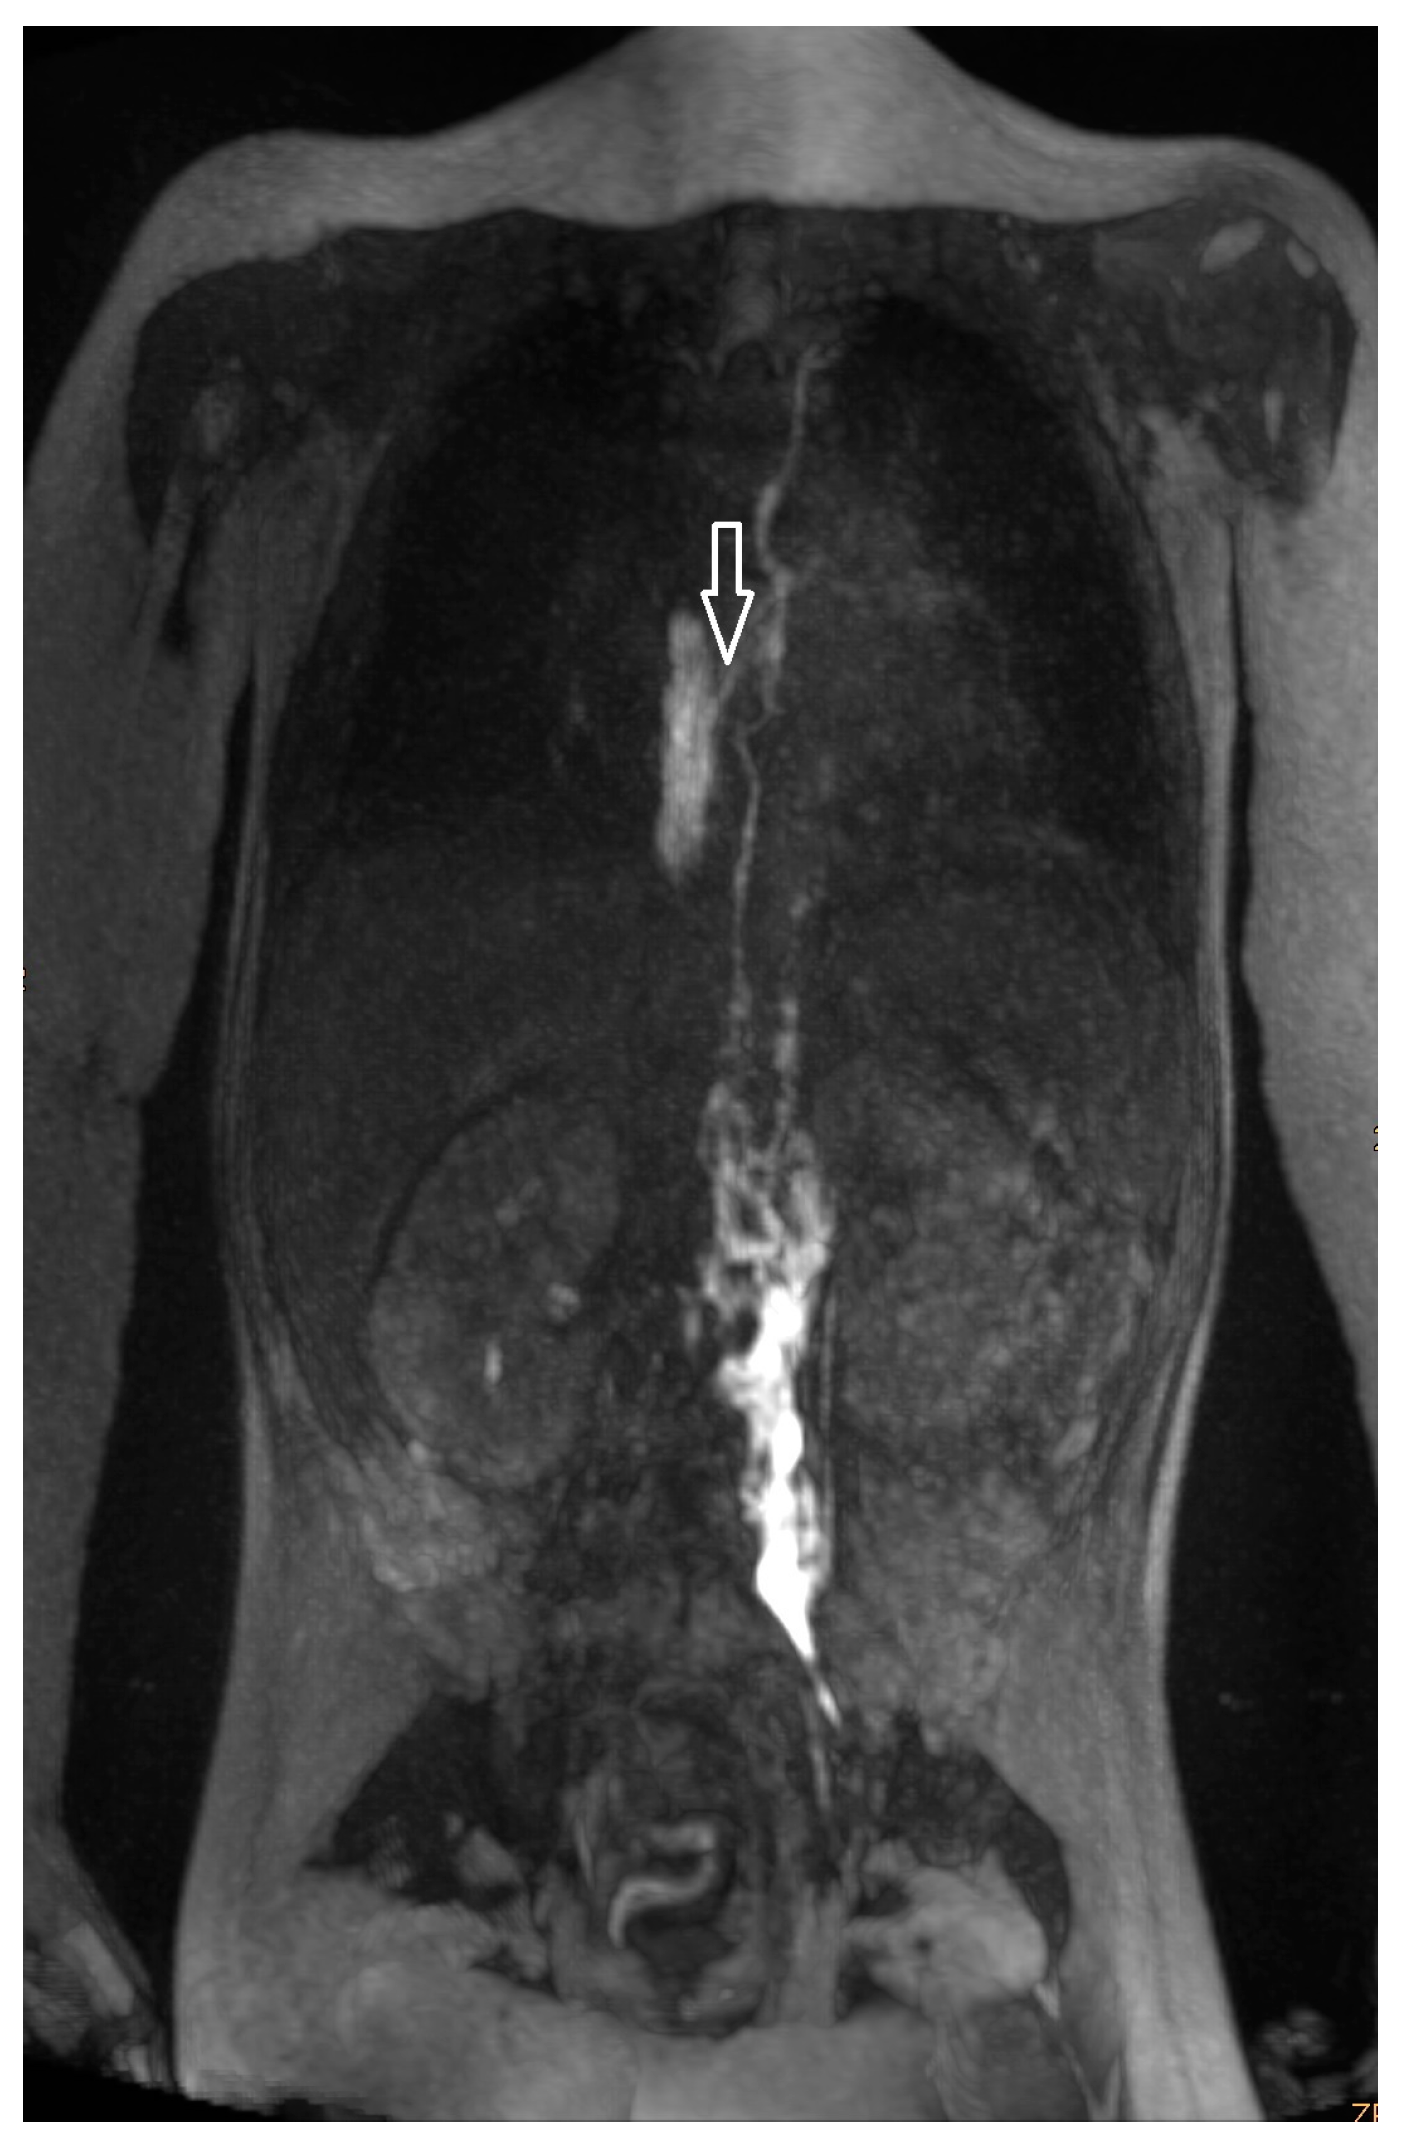

Figure 1.

Intercostal lymphatic flow (a, arrows point at it) and dermal backflow (b, * shows dermal backflow, # is the dilated lymphatic network, arrows point to a doubled thoracic duct with pulmonary effusions, + shows dermal effusions).

Noonan Syndrome: The details of our MR lymphography and dynamic contrast MR lymphangiography findings as well as the preprocedural management and outcome of the three patients with genetically confirmed Noonan syndrome are listed in Table 5. Figure 1a,b represent the typical findings of the Noonan syndrome patients. All three children’s lymphatics as well as lymphatic flow were severely abnormal. Lymphatic fistulas to the lung could be visualized in two children.

Increased signal of lymphatic structures on T2-weighted imaging was considered as abnormal lymphatics. Abnormal lymphatic flow was defined as contrast agent passing from the injection site to any anatomical structure not typically involved in centripetal lymphatic flow to the left venous angle, as previously described by David Biko. Based on the same publication, we described dermal backflow (Figure 1a) and intercostal lymphatic flow (Figure 1b) when intranodal contrast passed retrograde into the intercostal space along the chest wall or into the subcutaneous tissue [13].